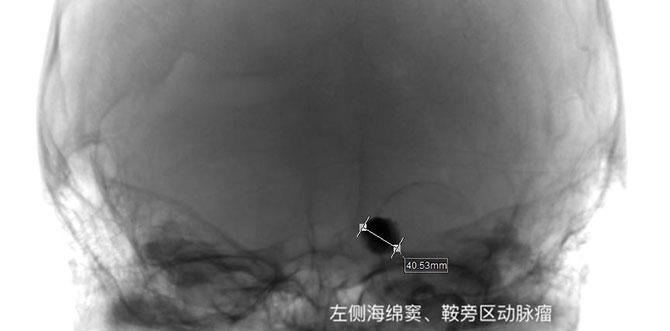

2023年底,小芸出现左侧眼睑下垂伴左侧面部疼痛、麻木,颅脑增强MR检查,提示左侧海绵窦、鞍旁区动脉瘤信号影(大小约40mm*32mm),较22年增大。血管外科团队再次为其安排了跨学科会诊,以确保小芸能够得到全面、精确的治疗。2024年初,由神经外科陈光忠主任主刀,为小芸行经导管颈动脉瘤栓塞术。术后恢复良好,出院时,小芸左眼睑下垂及左颜面部疼痛、麻木较前好转。

最后一次手术是“左颈内动脉瘤的栓塞术”,是针对小芸颈动脉瘤较前增大,术后颈动脉瘤得到了有效治疗,她的左眼视物模糊、左面部麻木症状有了明显好转。